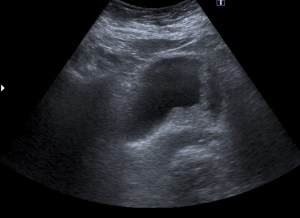

Tras el tratamiento de la recidiva y nefrostomía para la hidroureteronefrosis, vuelve acudir al hospital a los 9 meses por episodio de dolor en FD y malestar general. Se realiza una ecografía de urgencias.